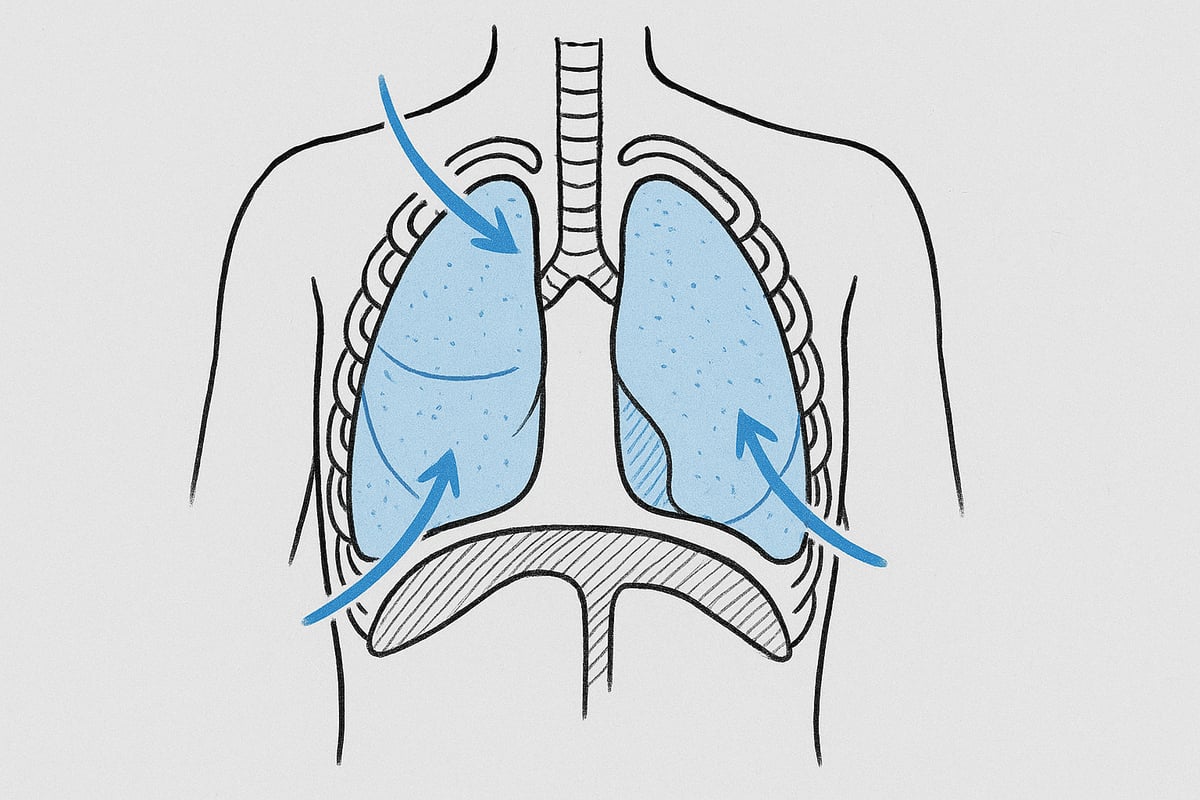

Indånding og udånding – trin for trin

Når du tager et åndedrag, arbejder flere dele af kroppen sammen. Diaphragma, den store flade muskel under lungerne, trækker sig sammen og bevæger sig nedad. Samtidig udvider de ydre interkostalmuskler mellem ribbenene brysthulen. Dette skaber et undertryk, så luften suges ind gennem næse eller mund og ned i lungerne.

Udånding sker, når diaphragma slapper af og bevæger sig opad. Brystkassen bliver mindre, og det skaber et overtryk, der presser luften ud af lungerne. Ved rolig vejrtrækning bruger kroppen næsten kun diaphragma. Hvis du trækker vejret dybt eller anstrenger dig, hjælper flere muskler til.